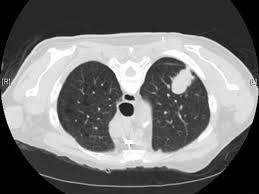

Early Signs Of Lung Cancer On Ct Scan - Google Says Its Ai Could Detect Early Signs Of Cancer Cnet : Lung nodules are tiny collections of tissue that appear in the lungs.. The larger nodules are more likely to be cancerous. How a ct scan works However, it can occur in other heart and lung diseases. Because many cases of lung cancer are not diagnosed early, as a first step in early detection, it is important to familiarize yourself with some of the early symptoms of the disease, which can include: Ct (or cat) stands for computed (axial) tomography.

One of the first signs of lung cancer that usually people tend to dismiss is a new cough that tends to persist. The ct scan might show signs of cancer, but that cancer might not be active for example, it could be scar tissue left over from cancer killed off by your treatment While it might seem obvious to assume that finding small tumors reduces one's likelihood of dying from lung cancer, this is incorrect. These small differences in lung nodules show on ct scans and can indicate if a nodule is cancerous or not. Changes in breathing can occur if lung cancer blocks or narrows an airway, or if fluid from a lung tumor.

What Are The Chances A Lung Nodule Or Spot Is Cancer Health Essentials From Cleveland Clinic from 2rdnmg1qbg403gumla1v9i2h-wpengine.netdna-ssl.com Doctors would often require you to take ct scans to be able to diagnose your condition properly. While it might seem obvious to assume that finding small tumors reduces one's likelihood of dying from lung cancer, this is incorrect. It takes pictures from different angles. Ct (or cat) stands for computed (axial) tomography. Screening external icon means testing for a disease when there are no symptoms or history of that disease. Using advanced medical imaging equipment known as a. In diagnosing lung cancer, but their role in checking whether treatment is working is unproven. Lung cancer screening is recommended for older adults who are longtime smokers and who don't have any signs or symptoms of lung cancer.

One of the first signs of lung cancer that usually people tend to dismiss is a new cough that tends to persist. Changes in breathing can occur if lung cancer blocks or narrows an airway, or if fluid from a lung tumor. This mass will look like a white spot on. A persistent cough not related to an illness. Ct (or cat) stands for computed (axial) tomography. As reviewed by bram van ginneken, phd, of the radboud university medical center in the netherlands, quantitative measures obtained from a chest ct scan may enable the early detection of different obstructive and interstitial lung diseases, such as chronic obstructive. Shortness of breath or becoming easily winded are also possible symptoms of lung cancer. The term tomography comes from the greek words tomos (a cut, a slice, or a section) and graphein (to write or record). The mayo clinic lists some of the common symptoms of lung cancer, which range from general hoarseness to coughing up blood. Each picture created during a ct procedure. When people experience signs and symptoms of lung cancer, the early ones may include any of the following: However, if it is an early warning sign of lung cancer, then this persistent cough will tend to linger. Without screening, 70 percent of lung cancers are found at a later stage when there is little chance for a cure.

Each picture created during a ct procedure. The main benefit of lung cancer screening is preventing death from lung cancer. Lung nodules are tiny collections of tissue that appear in the lungs. Lung cancer screening finds 80 percent of lung cancer at an early stage when it is more curable. Lung cancer can sometimes be detected in its early stages with a lung scan.

Patients with lung cancer may be asymptomatic in up to 50% of cases. Around 40 percent of lung nodules are cancerous (malignant). They appear due to scarring caused by a previous infection or a benign tumor. If the test finds cancer, treatment can start early. Each picture created during a ct procedure. It is sometimes called computerized tomography or computerized axial tomography (cat). Ldct scans can help find abnormal areas in the lungs that may be cancer. Find out if you are eligible for the early lung cancer detection program. The term tomography comes from the greek words tomos (a cut, a slice, or a section) and graphein (to write or record). Ct scans are inaccurate for treatment monitoring after cancer treatment, a ct scan is unable to determine whether masses leftover are cancerous: It is detectable by early symptoms such as constant coughing, chest pain, and many more. While it might seem obvious to assume that finding small tumors reduces one's likelihood of dying from lung cancer, this is incorrect. So what does a lung ct scan show?

What Are The Chances A Lung Nodule Or Spot Is Cancer Health Essentials From Cleveland Clinic from 2rdnmg1qbg403gumla1v9i2h-wpengine.netdna-ssl.com Ct scan for lung cancer. Ct scans are inaccurate for treatment monitoring after cancer treatment, a ct scan is unable to determine whether masses leftover are cancerous: It is sometimes called computerized tomography or computerized axial tomography (cat). Lung cancer screening is recommended for older adults who are longtime smokers and who don't have any signs or symptoms of lung cancer. A computer then combines these images into a detailed picture of your lungs. It takes pictures from different angles. Changes in breathing can occur if lung cancer blocks or narrows an airway, or if fluid from a lung tumor. The larger nodules are more likely to be cancerous.

Ct screening for lung cancer can reveal subtle early signs of disease in the lungs that extend beyond potential malignancy. Shortness of breath or becoming easily winded are also possible symptoms of lung cancer. Most doctors do not recommend pet/ct scans for routine follow up of patients after lung cancer treatment. The mayo clinic lists some of the common symptoms of lung cancer, which range from general hoarseness to coughing up blood. It takes pictures from different angles. a ct scan is needed if there is any concern. Lung nodules are tiny collections of tissue that appear in the lungs. Find out if you are eligible for the early lung cancer detection program. Pneumonia, pleural effusion, wheeze, lymphadenopathy are not uncommon. A persistent cough not related to an illness. Ct scans can detect cancer at a very small size. Patients with lung cancer may be asymptomatic in up to 50% of cases. It is used to look for early signs of lung cancer.